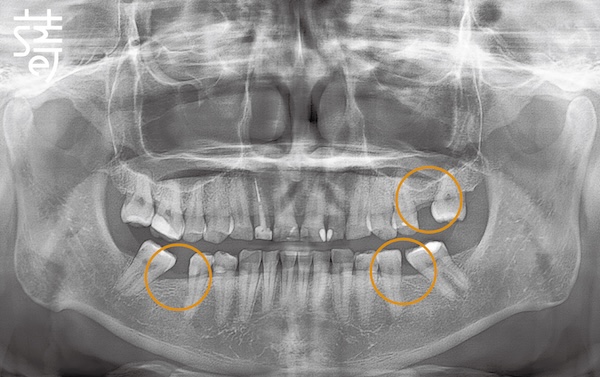

第二階段:植牙重建缺牙區 Stage Two: Implants for Missing Molars

針對缺牙已久的後牙區進行植牙,恢復後牙支撐,避免整體咬合繼續崩塌,讓口腔受力更均衡。

Implants were placed in the long-missing molar areas to restore support, prevent further bite collapse, and balance oral forces.

第一階段:隱適美矯正 Stage One: Invisalign Alignment

將牙齒重新排列整齊,調整上下咬合,把原本傾倒的第二大臼齒推回正確位置,為後續植牙和假牙重建打好基礎。

Teeth were realigned, the bite adjusted, and the previously tilted second molars repositioned, laying a solid foundation for implants and prosthetics.